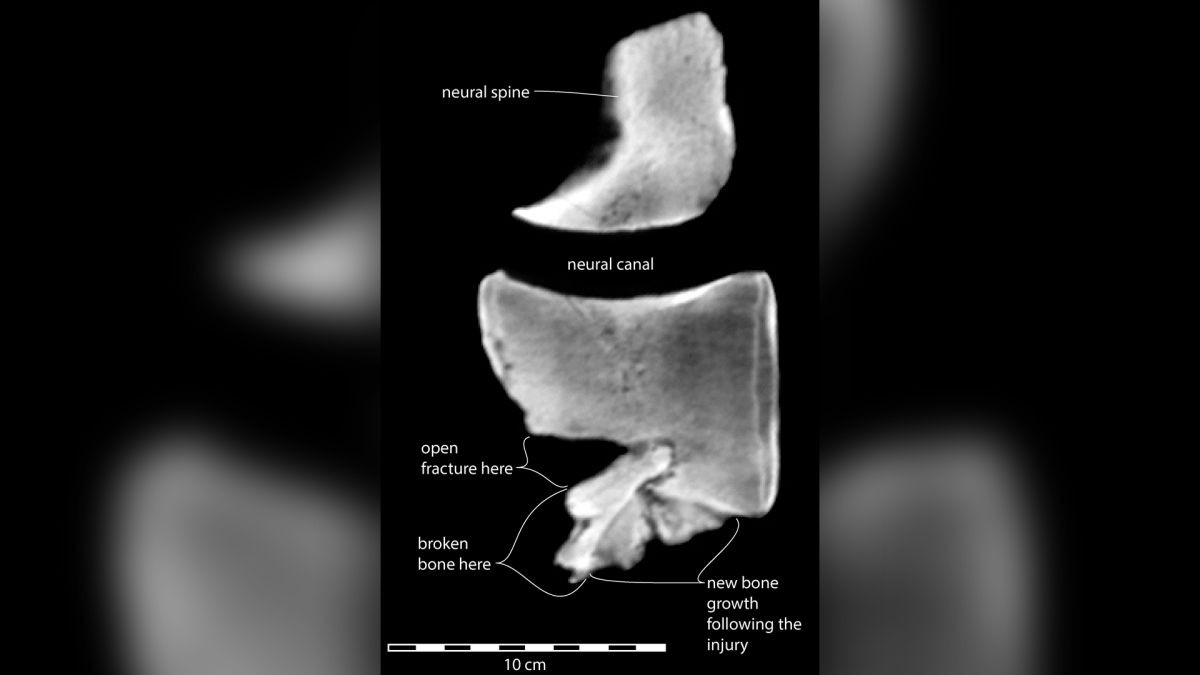

Hình ảnh quét cho thấy gãy xương trong một kiểu gãy trong đó đốt sống bị vỡ vụn và xẹp xuống - có hình dạng đặc biệt đến mức có thể nhận ra ngay lập tức. Godfrey nói: “Bất kỳ bác sĩ X quang nào cũng sẽ nhìn vào điều này và nhận ra bệnh lý”.

Các nhà khoa học cũng phát hiện ra rằng màng bao quanh xương, được gọi là màng xương, đã tạo ra xương mới sau chấn thương. Bất kể xương màng xương được hình thành để chữa lành vết thương, như thường thấy ở người, hay do nhiễm trùng hoặc viêm khớp, thì sự phát triển của xương mới sau chấn thương cho thấy cá voi sống được vài tuần sau khi bị gãy xương.